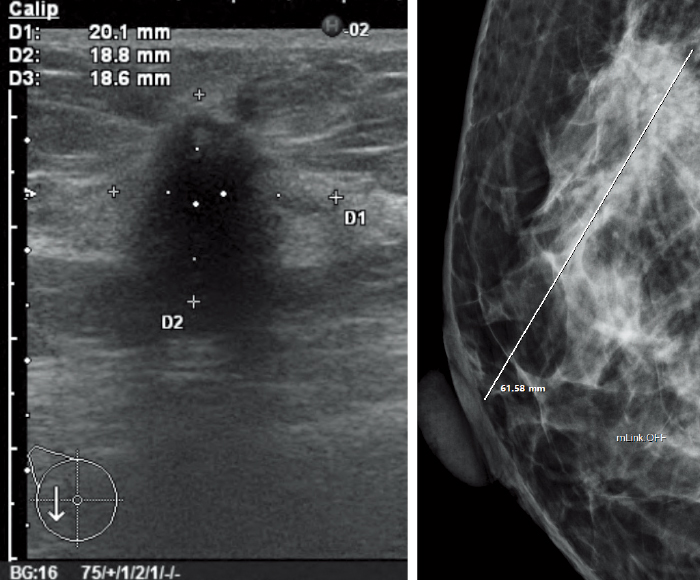

Support for users in conducting diagnosis with reading protocols tailored to mammographic diagnosis and smooth image displays. Customization for reading protocols includes configuration for making comparisons of current and prior images and for S-views synthesized from tomosynthesized images of AMULET Innovality and AMULET SOPHINITY.

![[image] Mammography (2D/Tomosynthesis/Comparisons with prior images)](https://asset.fujifilm.com/www/ar/files/2025-07/de9033bcde95317d22957c011cfe095f/pic_amulet-bellus-2_01.jpg)

The results from multiple exams for a patient are displayed in a list. Users can switch the displayed image with one of the selected images.

The thumbnail window allows users to instantly see all the images taken for each individual exam in a single one view. Each image can be easily selected and displayed by dragging and dropping.

Various images, such as MG, BT, MR, CT, US, etc., are available for mammography diagnosis at the same time.